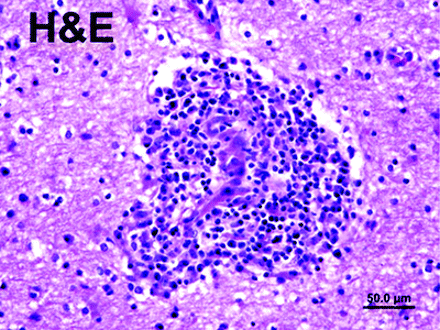

Venkataramana等人描述三个患者临床上明显的神经症状与艾滋病毒感染免疫重建炎性综合症和审查。这种潜在的致命综合症是矛盾与成功控制HIV病毒的复制与抗逆转录病毒药物。

这种免疫重建炎性综合征(IRIS)或免疫重建综合症,特点是机会性感染的外观(OI)或非感染性炎症性疾病在几周内从HAART治疗的开始。它越来越被认为是一个独立的原因严重的艾滋病发病率和死亡率,尤其是主题与非常低的CD4细胞启动时鸡尾酒疗法。1、2

不同程度的感染分枝杆菌、隐球菌、疱疹病毒、乙肝和丙肝病毒,与虹膜JC病毒最常见的报告。大部分先前那些OI治疗的患者的影响,但在一些科目没有之前的历史。在后者的情况下严重的渐进多焦点的脑白质病。1的光谱表现归因于虹膜继续扩张,但很明显,神经系统通常是一个目标。1、2

虹膜也被卷入一些无法解释的炎性疾病,包括大脑血管炎,一种传染性剂不能被识别。